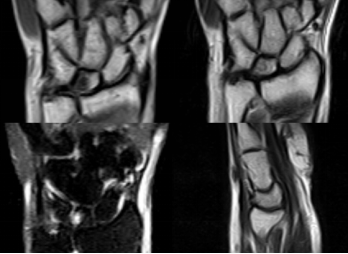

舟月骨缺血性坏死

腕关节发生骨缺血坏死的常见部位为舟骨和月骨

好发于20-30岁手工劳动者,也常见于腕部急性创伤和月骨骨折脱位后

男性多见

X线表现为病变早期骨形态尚可,骨质密度增高,其内可见囊样透亮影,进展期骨质塌陷,周边关节间隙增宽;MR对早期骨缺血坏死较敏感

手足短骨解剖及常见疾病的影像学表现

舟骨缺血性坏死

54Y,M 月骨缺血性坏死

65Y,M,左手疼痛2个月